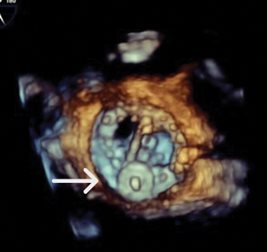

A transesophageal echocardiogram (TEE) demonstrates moderate-to-severe paravalvular leak adjacent to the bioprosthetic aortic valve, localized near the left coronary cusp (see Fig. 1).

Fig. 1. Deep transgastric view of the aortic valve by transesophageal echocardiography demonstrates severe paravalvular leak. In this image, color represents regurgitant flow from the aorta into the left ventricle during diastole.